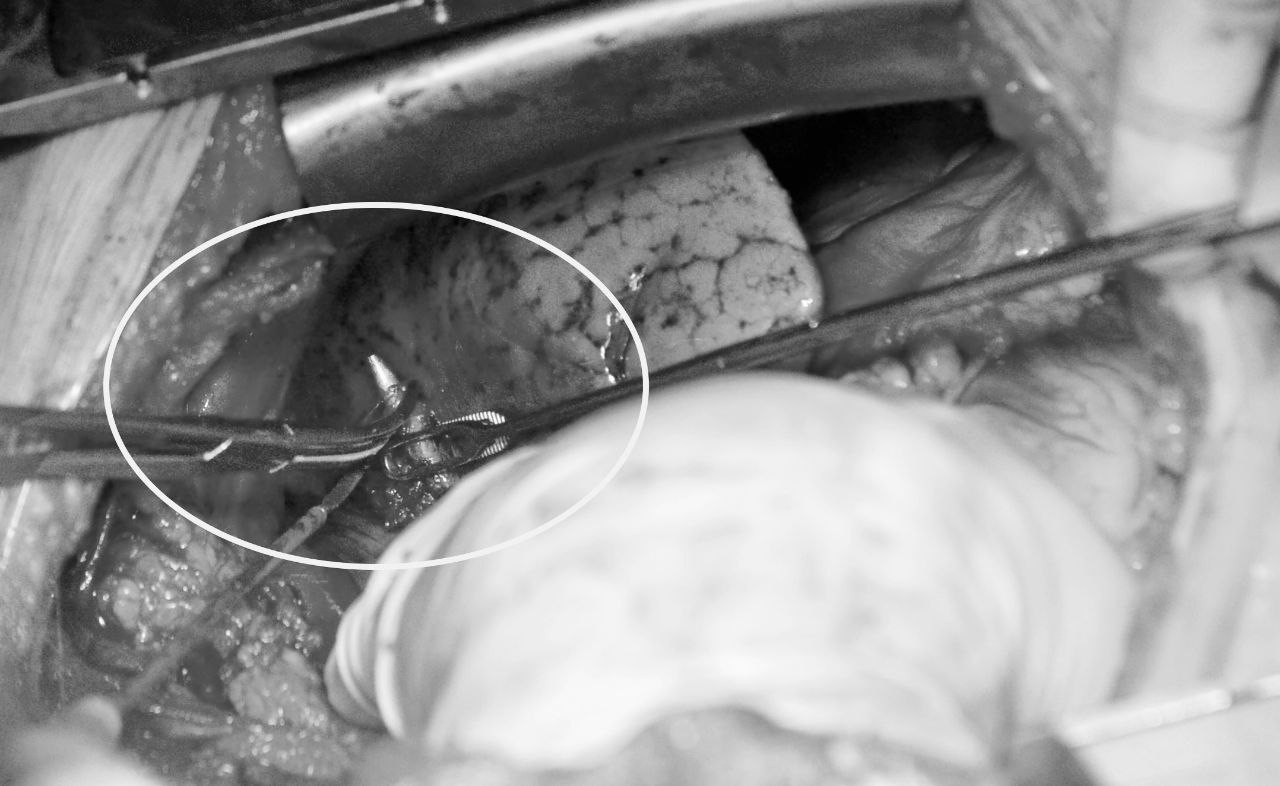

Пуля размером 5,5 сантиметра находилась между сердцем и корнем лёгкого. Запаяна была соединительной тканью. Хирургам предстояло извлечь инородное тело не повредив корень лёгкого и сердечную мышцу.

Очень тщательно шаг за шагом, миллиметр за миллиметром кардиохирурги шли к верхушке пули, чтобы выделить её и извлечь. Но снаряд был настолько скользким, что невозможно было удержать его хирургическим инструментом. Пришлось дополнительно рассекать ткани и осторожно выделять инородное тело полностью.

– Пуля была очень коварная, казалось она издевается над нами. Пять раз мы её захватывали зажимом, но она выскальзывала. Острой верхней частью снаряд находился в корне лёгкого, а широким основанием припаян был к сердцу. Я ещё никогда не видел, чтобы пуля так «играла» с хирургами. Операция шла уже около трёх часов, когда промелькнуло в мыслях отчаяние, что она неудалима. Из-за её местоположения был огромный риск получить кровотечение с угрозой для жизни пациента. В последний момент мне удалось рассечь ткани электроножом и коварный снаряд открылся. Нам удалось его перехитрить. Такое я видел впервые в своей практике. Операция длилась более четырёх часов. Интересно то, что изначально пуля находилась справа у сердца, а потом она сместилась влево, – прокомментировал ход операции начальник кардиохирургического центра госпиталя, доктор медицинских наук, профессор Александр Лищук.

Операция проведена в гибридном операционном комплексе госпиталя, оснащённом самыми современными диагностическими приборами и аппаратами. Это позволило точно определить место нахождения пули, которая каждый раз при дыхании пациента смещалась. Потребовалось постоянно наводить ангиографическую систему для того, чтобы смещённый верхний острый конец снаряда выводить из ткани лёгкого.